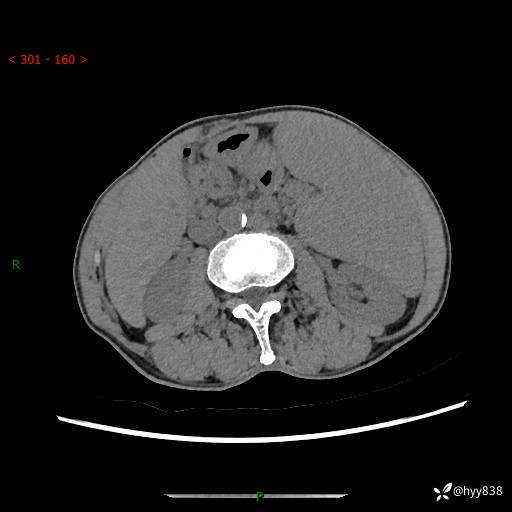

老年男性,脾大并脾脏弥漫粟粒状低密度,淋巴瘤 VS 肉芽肿 VS 血管瘤---结果公布

简要病史: 患者于3月前无明显诱因出现脾大,伴腹部轻微不适,具体不详,无腹痛、腹泻、腹胀,无头晕、头痛、乏力,无恶心、呕吐、呕血,无胸闷、气短、胸痛不适

上腹部CT平扫+增强